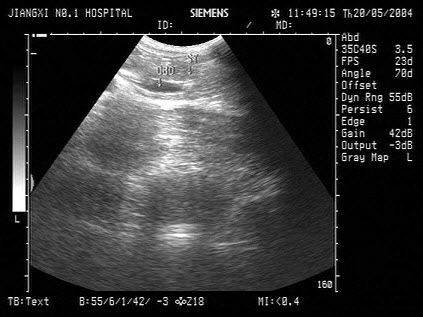

20、单项选择题

女,25岁,因急性胰腺炎禁食5天。声像图如图所示。结合超声声像图,诊断为()

A.胆囊泥沙样结石

B.胆囊内胆汁淤积

C.胆囊多发性息肉

D.胆囊多发性胆固醇结晶

E.胆囊癌

21、单项选择题